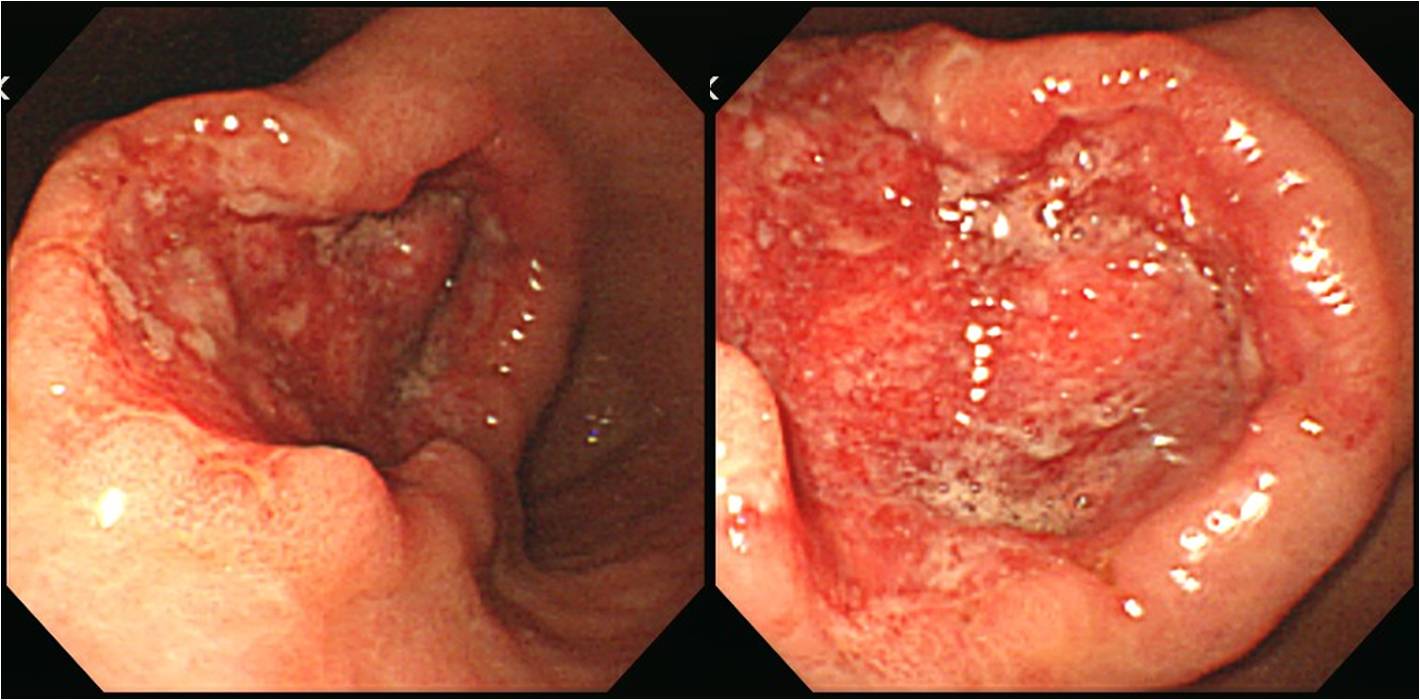

°ËÁø ³»½Ã°æ½Ç¿¡¼­´Â ¾ÏÀÌ ¹ß°ßµÇ¸é AGCµµ EGC¶ó°í ±â¼úÇϰí Å©±âµµ ÀÛ°Ô ¾²´Â °æ¿ì°¡ ¸¹Àº °Í °°½À´Ï´Ù. ¾Æ¹«·¡µµ ȯÀÚ¿¡°Ô ¼³¸íÇϴµ¥ ºÎ´ãÀÌ ¸¹±â ¶§¹®À̰ÚÁö¿ä. ¾Æ·¡ °æ¿ì´Â 2.5cm ¾ÏÀ¸·Î ÀÇ·ÚµÈ ºÐÀε¥ Á¦°¡ º¸±â¿¡´Â Á·È÷ 5-6cm´Â µÇ¾î º¸¿´½À´Ï´Ù. CT¿¡¼­´Â ÀÌ¹Ì °£ ÀüÀ̰¡ ½ÉÇß½À´Ï´Ù. ¿Ü·¡ ³»½Ã°æ½ÇÀÌ´ø °ÇÁø ³»½Ã°æ½ÇÀÌ´ø º´¼ÒÀÇ Å©±â´Â °´°üÀûÀ¸·Î »ç½É¾øÀÌ ¾²´Â °ÍÀÌ ÁÁ°Ú½À´Ï´Ù.

¾Æ·¡ Áõ·Êµéµµ Å©±â ÃøÁ¤ÀÇ ¿ÀÂ÷°¡ ÇöÀúÇß´ø °æ¿ìµéÀÔ´Ï´Ù.

2 cm ¹Ì¸¸ÀÇ ÀÛÀº À¶±â+ÇÔ¸ôº´¼Ò·Î Æò°¡µÇ¾ú½À´Ï´Ù. ±×·¯³ª ½ÇÁ¦·Î´Â À§ °ÅÀÇ Àüü¸¦ Â÷ÁöÇÏ´Â º¸¸¸ 4Çü ÁøÇ༺ À§¾Ï¿¡ ÀÛÀº ±Ë¾çºÎÀ§°¡ ÀÖ¾ú´ø °ÍÀ̾ú½À´Ï´Ù. SRC, 17x15 cm, extension to subserosa, LN 17/35, perineural invasion (+)

±Ë¾ç¸¸ º¸°í 1.5 cm¶ó°í Çߴµ¥ ¼ö¼ú °á°ú ÈξÀ Å« ¾ÏÀ̾ú½À´Ï´Ù. ±Ë¾ç ÁÖº¯¿¡µµ ÀÌ»óÀÌ ÀÖ¾ú´ø °ÍÀÔ´Ï´Ù. P/D, 4.0 x 2.2 cm, pT1a (lamina propria), LN 0/55

±Ë¾ç¸¸ º¸°í ±Ë¾ç Á÷»óºÎ¿¡ clippingÀ» Çߴµ¥ ¼ö¼úÀ» ÇØº¸´Ï clipping ºÎÀ§¸¦ Æ÷ÇÔÇÏ¿© ÈξÀ ´õ Å« ¾ÏÀ̾ú½À´Ï´Ù. AGC, mimicking early gastric carcinoma IIc+III, posterior wall and lesser curvature of mid body to antrum, Signet ring cell carcinoma, diffuse type, 8.2x6.8cm, extension to inner proper muscle layer, 0/42